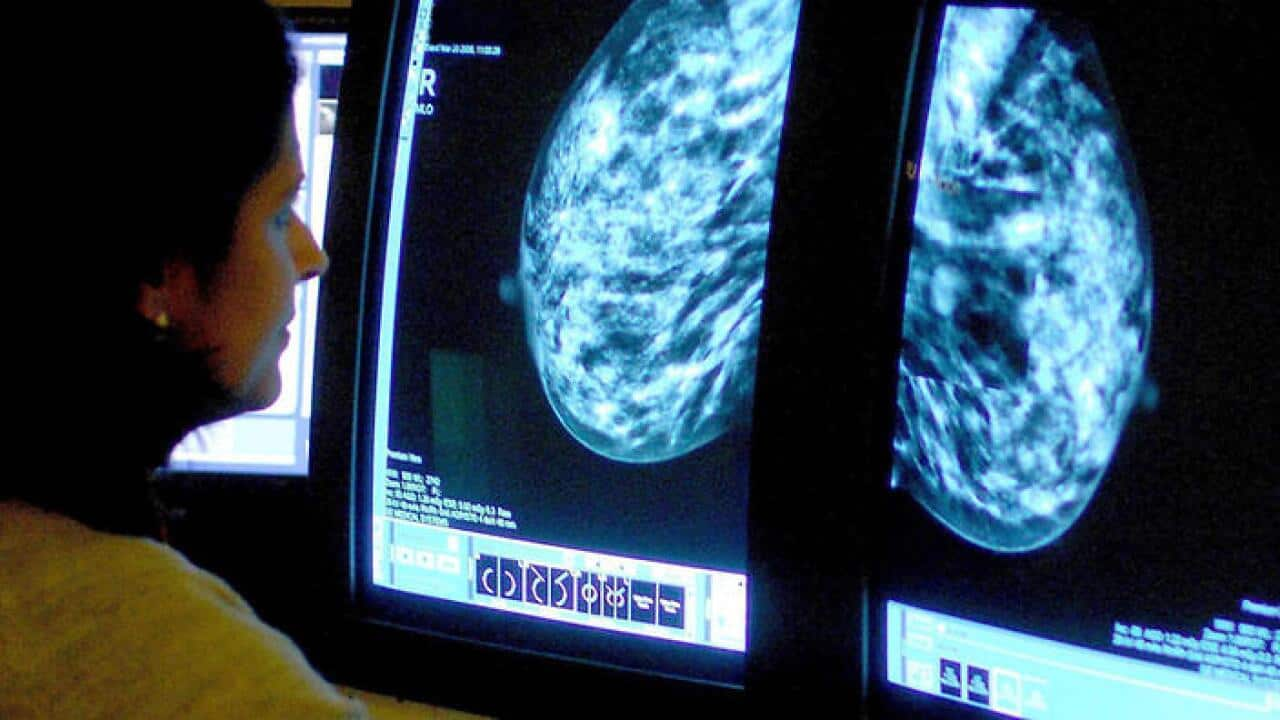

For a pregnant breast cancer patient, and should she wants to preserve the right of giving birth, what can a gynecologist do with today's medical technology? Gynecology specialist, Dr Peter Leung, interviewed by Thomas Sung regarding this topic.